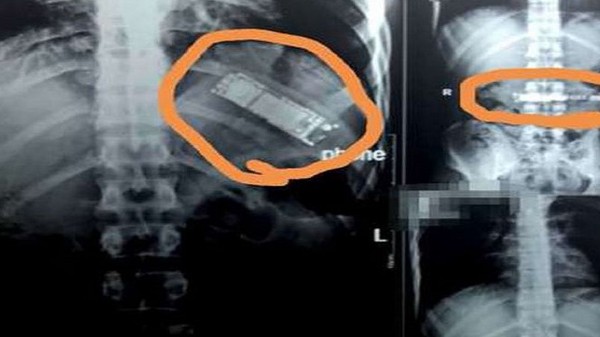

ವ್ಯಕ್ತಿಯೊಬ್ಬನ ಹೊಟ್ಟೆಯೊಳಗೆ ಆರು ತಿಂಗಳುಗಳ ಕಾಲ ಇದ್ದ ಮೊಬೈಲ್ ಅನ್ನು ಹೊರತೆಗೆದಿರುವ ಘಟನೆ ಈಜಿಪ್ಟ್ನಲ್ಲಿ ನಡೆದಿದೆ. ಹೊಟ್ಟೆ ನೋವಿನ ಕಾರಣಕ್ಕೆ ಆಸ್ಪತ್ರೆಗೆ ದಾಖಲಾಗಿದ್ದ ವ್ಯಕ್ತಿಯ ಹೊಟ್ಟೆಯೊಳಗೆ ಮೊಬೈಲ್ ಕಂಡ ವೈದ್ಯರು ಶಾಕ್ ಆಗಿದ್ದಾರೆ. ಹೊಟ್ಟೆಯ ನೋವು ಎಂದು ಆಸ್ಪತ್ರೆಗೆ ಬಂದ ವ್ಯಕ್ತಿಯ ಹೊಟ್ಟೆ ಭಾಗವನ್ನು ಎಕ್ಸ್ರೇ ತೆಗೆದಾಗ ಆತನ ಹೊಟ್ಟೆಯಲ್ಲಿ ಮೊಬೈಲ್ ಇರೋದು ಪತ್ತೆಯಾಗಿದೆ. ಇಲ್ಲಿ ಗಮನಿಸಬೇಕಾದ ಮತ್ತೊಂದು ವಿಚಾರ ಏನೆಂದರೆ ಆರು ತಿಂಗಳ ಹಿಂದೆ ಆತನೇ ಫೋನ್ ಅನ್ನು ನುಂಗಿದ್ದ ಎನ್ನಲಾಗಿದೆ.

ಈಜಿಪ್ಟ್ನಲ್ಲಿ ನಡೆದಿರುವ ಈ ಘಟನೆ ನಿಜಕ್ಕೂ ಅಚ್ಚರಿಯೆನಿಸಲಿದೆ. ಮೊಬೈಲ್ ಅನ್ನು ನುಂಗಿದ ನಂತರ ಆತ ಆರು ತಿಂಗಳುಗಳ ಕಾಲ ಹೇಗಿದ್ದ ಅನ್ನೊದೇ ಅಶ್ಚರ್ಯಕರವಾಗಿದೆ. ಆದರೂ ಕೂಡ ಆತ ಮೊದಲಿಗೆ ವೈದ್ಯರ ಬಳಿ ಮೊಬೈಲ್ ನುಂಗಿರುವ ವಿಚಾರ ಬಾಯ್ಬಿಟ್ಟಿಲ್ಲ. ಬದಲಿಗೆ ಹೊಟ್ಟೆ ಕೆಟ್ಟಿದ್ದು, ವಿಪರೀತ ನೋವು ಎಂದು ಆಸ್ಪತ್ರೆಗೆ ದಾಖಲಾಗಿದ್ದಾನೆ. ಆದರೆ ವೈದ್ಯರು ಎಕ್ಸ್ರೇ ತೆಗೆದು ನೋಡಿ ಆತನ ಹೊಟ್ಟೆಯಲ್ಲಿ ಫೋನ್ ಕಂಡು ಆಘಾತಕ್ಕೊಳಗಾಗಿದ್ದಾರೆ. ಇದೆಲ್ಲಾ ನಡೆದ ಮೇಲೆ ಆತ ತಾನು ಆರು ತಿಂಗಳ ಹಂದೆ ಫೋನ್ ನುಂಗಿರುವ ಘಟನೆ ತಿಳಿಸಿದ್ದಾನೆ.